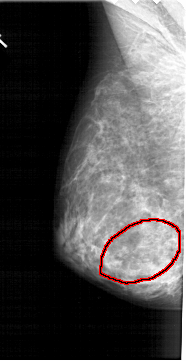

A_1379_1.LEFT_CC

LEFT_CC LINES 5086 PIXELS_PER_LINE 2596 BITS_PER_PIXEL 12 RESOLUTION 43.5 OVERLAY

FILE: A_1379_1.LEFT_CC.OVERLAY

TOTAL_ABNORMALITIES 1

ABNORMALITY 1

LESION_TYPE MASS SHAPE IRREGULAR MARGINS ILL_DEFINED

ASSESSMENT 4

SUBTLETY 4

PATHOLOGY BENIGN

TOTAL_OUTLINES 1

BOUNDARY